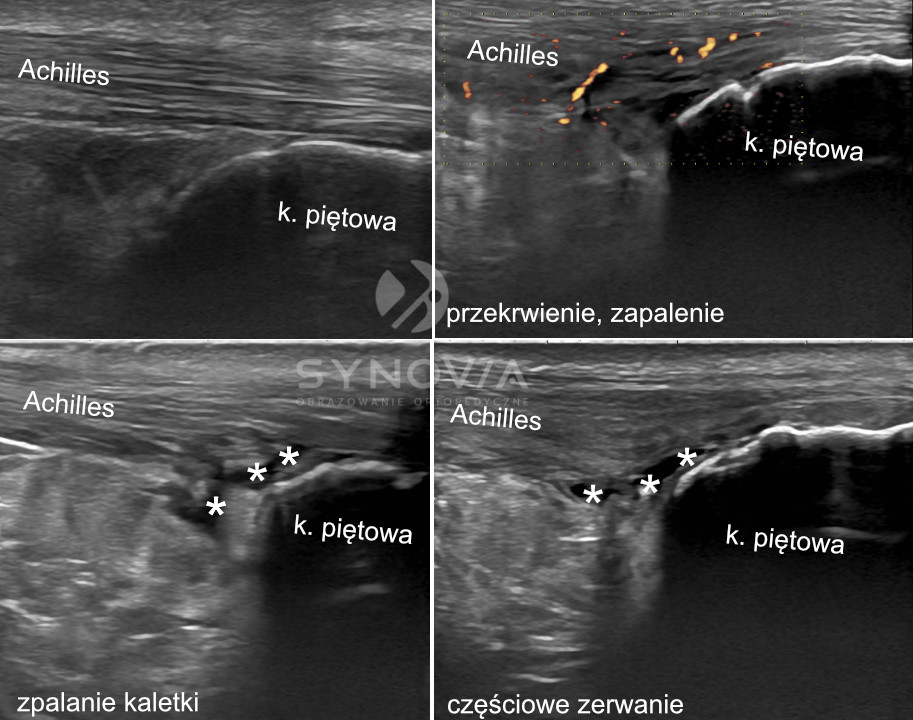

USG

Co widać: Pogrubienie ścięgna, zaburzenie struktury włókienkowej, hipoechogeniczne obszary naderwań, wzmożone unaczynienie, płyn w kaletkach.

Czy USG pozwala odróżnić ostrą fazę zapalenia od zmian przewlekłych?

Tak. W badaniu USG można ocenić cechy aktywnego zapalenia, takie jak obrzęk, przekrwienie w Dopplerze czy rozwarstwienie włókien rozcięgna. Ma to kluczowe znaczenie przy planowaniu leczenia, ponieważ inne metody stosuje się w ostrym zapaleniu, a inne w przewlekłej entezopatii.